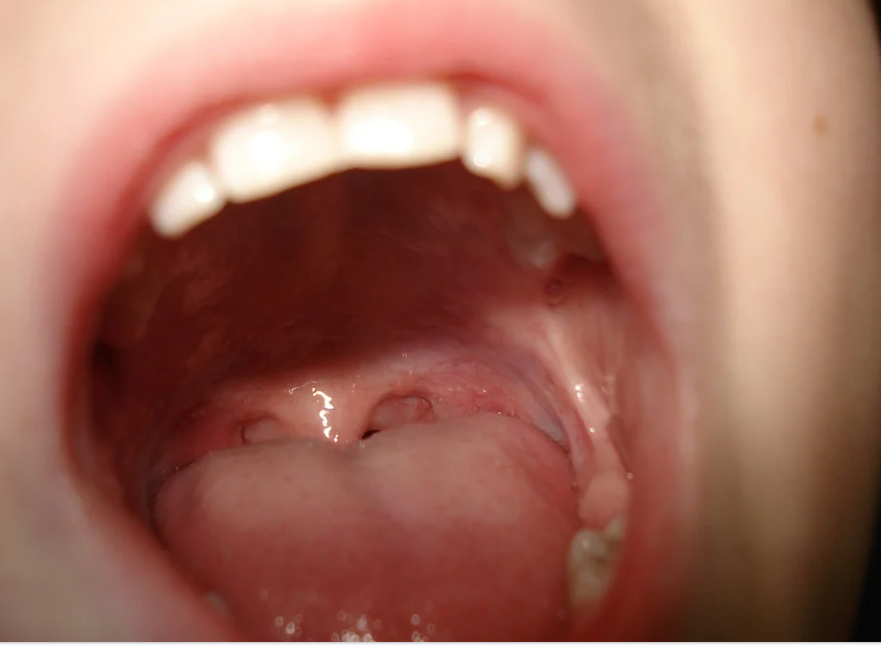

혀 건강상태 체크

혀 건강상태 체크로 건강관리하는 방법에 대한 포스팅으로 건강관리에 도움을 드리고자 합니다. 건강한 혀는 테두리가 매끄럽고 설태가 얇고 고르게 퍼져 있으며 촉촉한 상태입니다. 주로 구강위생과 관련되는 혀는 꼼꼼한 양치질이 중요합니다.

2. 혀의 증상별로 체크하기